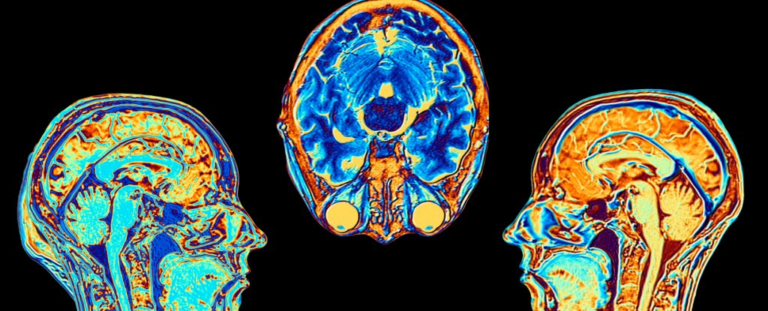

Довгий COVID може виправдати свою назву. Нове дослідження показує, що певні симптоми захворювання, такі як запаморочення мозку, все ще можуть спостерігатися у…